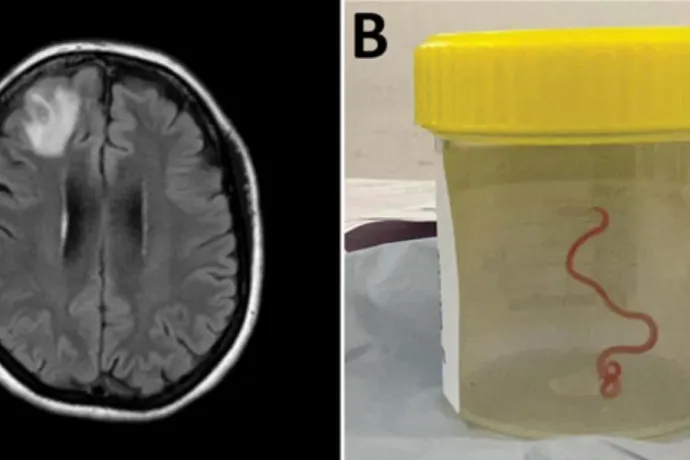

Istenem, nem hiszem el, mit találtam a fejében: él és vonaglik!

Először fedeztek fel emberi agyban egy alapvetően kígyókon élősködő orsóférget.